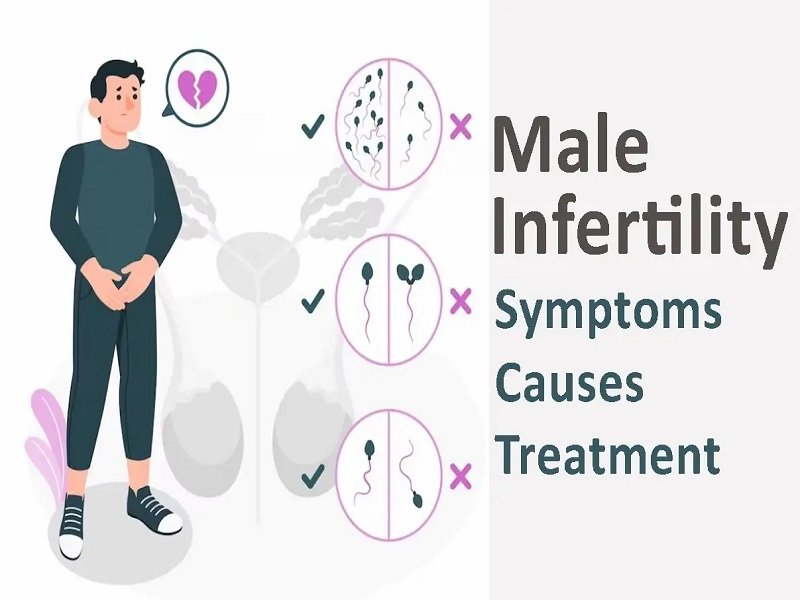

Male infertility affects a man's ability to make his wife pregnant.These infertility issues are underlying conditions that are related to the reproductive organs of a man. The major causes of male infertility are related to some deficiencies in semen and its quality.